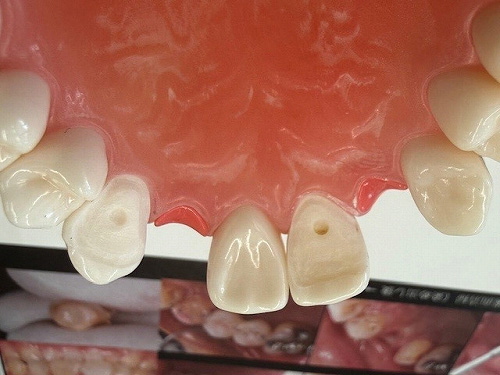

何とか保存出来た外部吸収

以前ブログにさせてもらった。

術前

2025 EEdental IZY (1).jpg

根管充填後

2025 EEdental IZY (4).jpg

術後1年

2026 EEdental IZY.jpg

痛みや腫れも出ておらず使えているようです。

ホント外部吸収の治療は困難を極めるのと、持つまでの治療となってしまいますが何とか保存出来てよかったです!